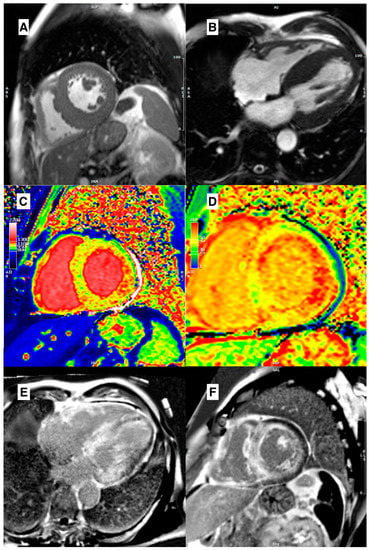

2. HCM Phenocopies (Similarities and Differences)

3. Cardiovascular Magnetic Resonance

3.1. Morpho-Functional Features in Hypertrophic Phenotypes

3.4. Role of Parametric Mapping